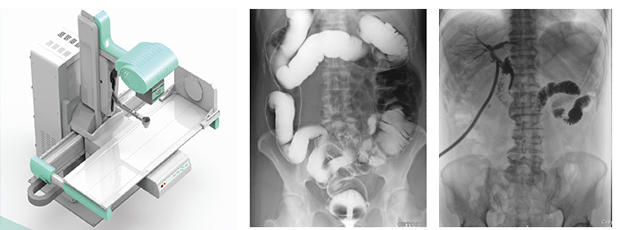

3、要擁有適宜床體高度的動態(tài)檢查床及全面的床體運動功能,以輕松實現(xiàn)各種普通及特殊造影檢查,如食道造影、消化道造影、結腸雙對比造影、T管造影、靜脈腎盂造影(IVP)等。同時動態(tài)dr要支持醫(yī)生回放造影視頻,并可以抽幀,輔助疾病診斷。